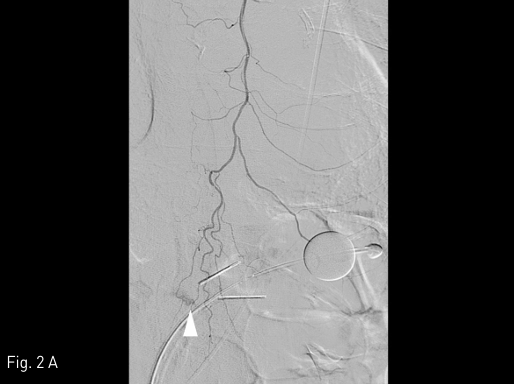

Fig 1A

Contrast-enhanced CT study was performed to find out the presence of active bleeding. Comparing the pre-contrast (A) and arterial phase (B) images, contrast extravasation (arrow) between the skin and the packing gauze (arrowheads) is noted around the gastrostomy site.